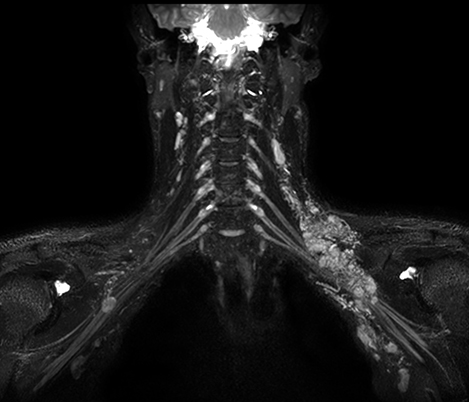

Klinische Fallbeispiele für nahezu jede anatomische Struktur Sehen Sie sich mehr als 100 klinische Fallbeispiele von Kollegen auf der ganzen Welt an, die zeigen, wie die digitale MR-Technologie von Philips Ihre Anforderungen in der Bildverarbeitung unterstützt.